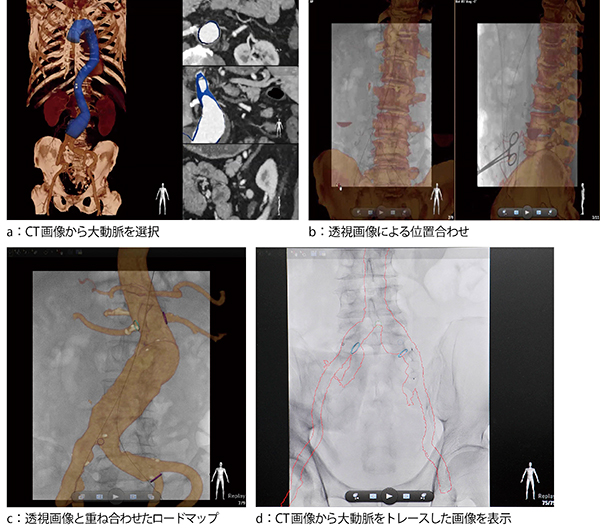

症例1:VesselNavigatorによるステントグラフト内挿術のナビゲーション

岡学内講師が選定理由に挙げたように,ハイブリッドOR向けのアプリケーションが充実しているのもAlluraClarity FD20のアドバンテージである。その一つVesselNavigatorは,EVARやTEVARにおいてCT・MR画像とのフュージョン画像による3Dロードマップを高精度で自動処理するアプリケーションである。従来の3Dロードマップは,術前の撮影においてターゲットになる血管を抽出して背景骨などを調整していたほか,手技中にも3D情報を得るために3D撮影を行っていた。VesselNavigatorを用いれば,手間のかかる画像処理や3D撮影が不要となり,2方向からの透視撮影だけで手技中の透視画像にCT・MR画像を重ね合わせて表示できる。ナビゲーション中,CT・MR画像はCアームやテーブルの動作,視野サイズの切り替えにも速やかに追従する。

「実際の手技では,血管撮影装置の透視画像だけでは情報が不足しており,術前のCT画像などの情報が必要となります。特に,私たちにとって重要なのは,リアルタイムに透視画像とフュージョンすることです。VesselNavigatorでは,術前のCT画像やその画像を基に作成した輪郭だけのデータを透視画像に自動的に重ね合わせ,Cアームの動きに同期して展開するので,複雑な血管の分枝も容易に把握でき,手技を進める上で役立っています。そのため,何度も造影する必要がなくなりました。造影剤の使用量は以前メインで使用していた外科用モバイルCアーム装置と比較して,1/3程度にまで抑えられています。AlluraClarity FD20は,被ばく量を抑えても高画質が得られるので,造影剤量と被ばくの両方を低減した手技ができており,患者さんにとっても大きなメリットになっていると思います」